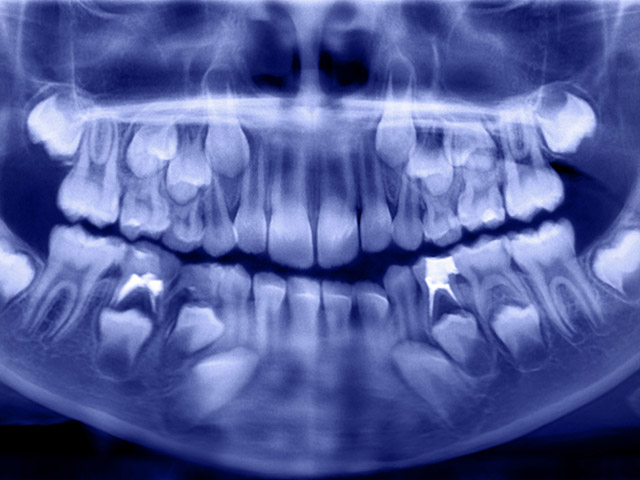

Зубы человека перестают расти еще в детстве, тогда как у многих животных, таких как верблюды, ламы, крысы, мыши и прочие грызуны, часть из них продолжает расти на протяжении всей жизни. Это возможно благодаря тому, что в основании каждого зуба присутствует несколько колоний "взрослых" стволовых клеток, способных производить все типы его тканей. Эти клетки, как давно знают ученые, присутствуют и в зубах человека, однако они, по пока непонятным причинам, не участвуют в их починке или замене выпавших или удаленных резцов, клыков или моляров. Четыре года назад биологи из Гарварда обнаружили, что их можно заставить это сделать, если обработать стволовые клетки при помощи лазерных импульсов.

Руководствуясь этой идеей, ученые пробурили отверстия в коренных зубах нескольких крыс и заполнили их двумя составами – препаратом, который обычно применяется для заполнения очищенных каналов при удалении нерва, и его смесью с Dlk1. Во втором случае эта процедура привела к заживлению пульпы и восстановлению дентина, что подтвердило, что данный белок можно применять для восстановления зубов.